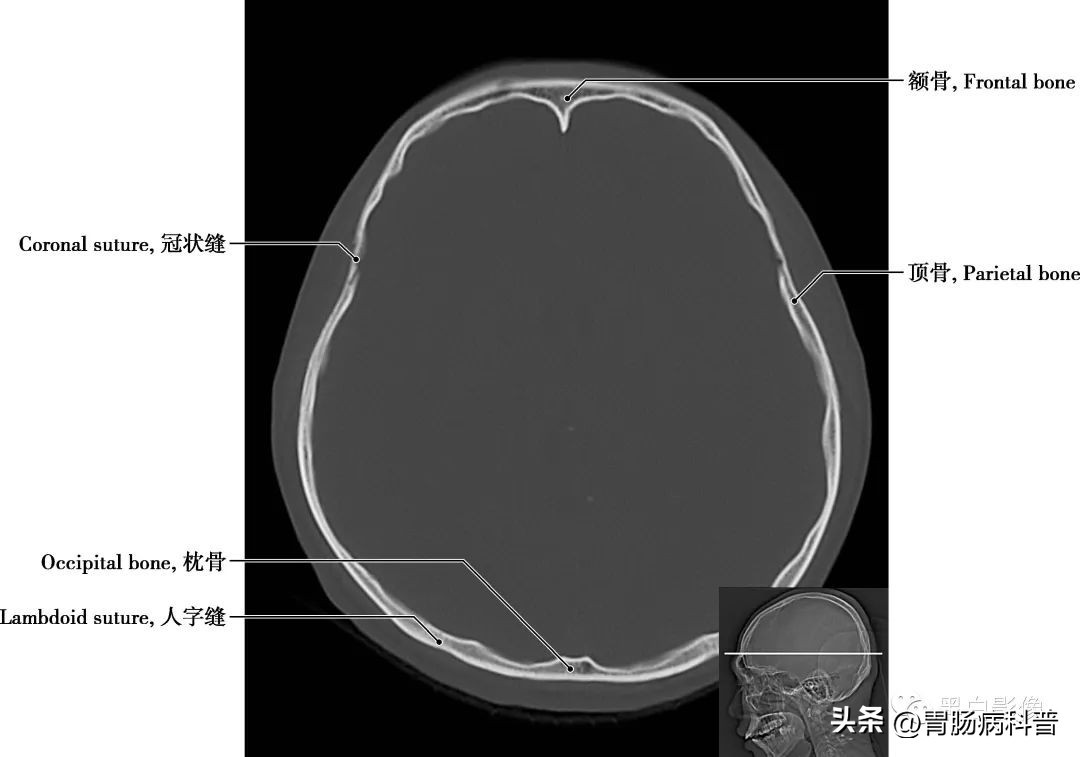

图1-2-4 经中央旁小叶下部轴位切面

冠状缝 顶骨与额骨之间的骨缝,呈冠状位走行